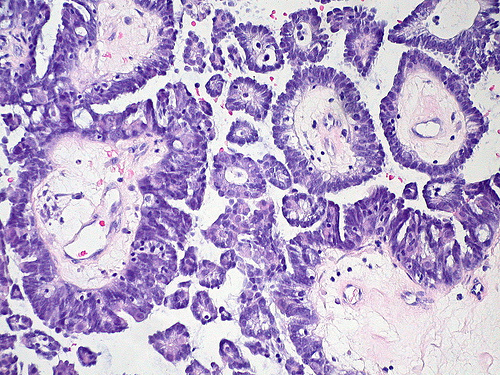

photo credit: euthman